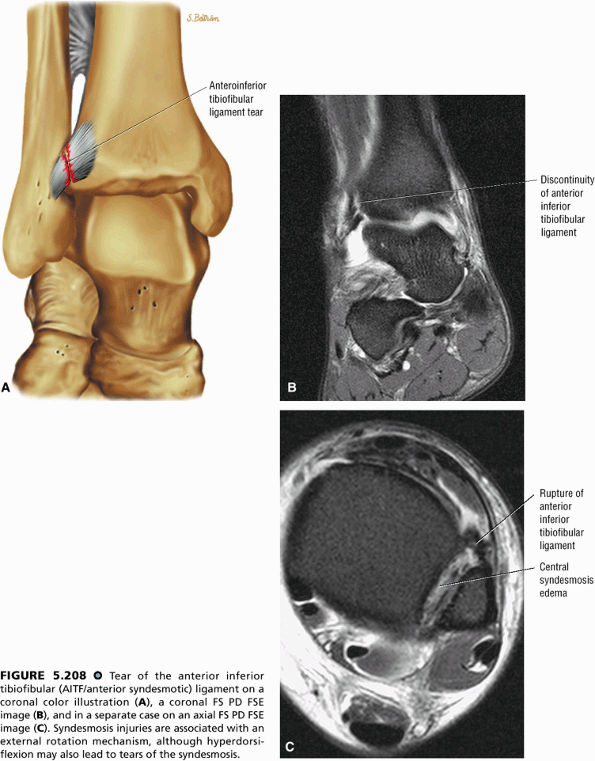

The syndesmotic ligaments consist of the anterior syndesmotic or anterior inferior tibiofibular ligament and the posterior syndesmotic or posterior inferior tibiofibular ligament, the interosseous membrane, and the transverse tibiofibular ligament.

-

The transverse tibiofibular ligament represents the posterior labrum of the ankle and projects inferior to the posterior tibial margin.